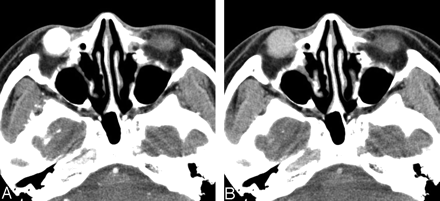

A and B, Case 6. Solitary fibrous tumor of the lower eyelid in a 40-year-old man. Axial early-phase (A) and late-phase (B) CT scans show a 20-mm well-defined ovoid soft tissue mass on the right lower eyelid. Marked homogeneous enhancement is seen on early-phase CT scan (A), followed by rapid washout of contrast material on late-phase CT scan (B).

On visual inspection, all 6 lesions showed marked homogeneous (n = 4) or heterogeneous (n = 2) enhancement on postcontrast CT and MR images (Figs 1B–H, 2A–D, 3A). In 3 patients examined with dual-phase CT, all lesions demonstrated rapid enhancement and early washout of contrast material (Figs 1, 3), and their time-attenuation curves revealed the very similar enhancing characteristics to those of the internal carotid artery (Fig 1E).